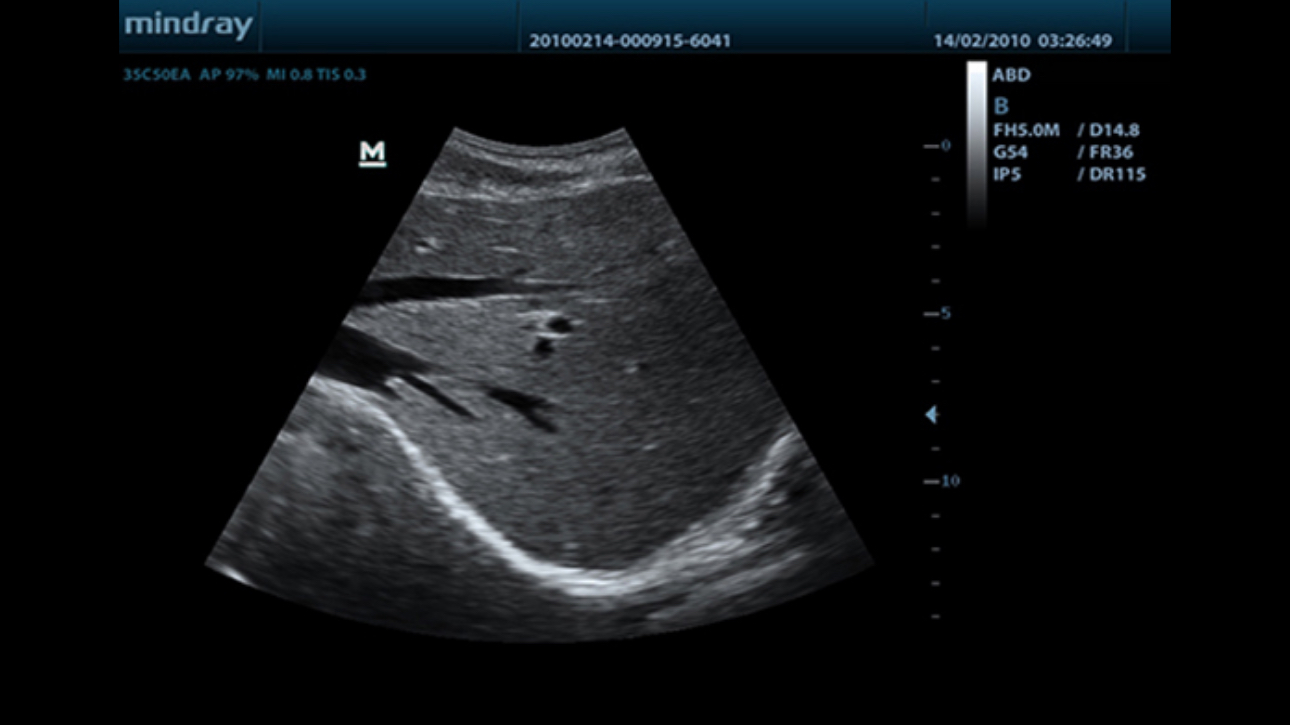

MindrayŌĆÖs new generation of black & white ultrasound system, DP-50, is equipped with advanced imaging technologies allowing deeper penetration and faster image acquisition with higher resolution.? A smart new shape, enhanced mobility and convenient operation make DP-50 well suited for all clinical settings.

Discover better diagnostic information through extended view of the anatomical structure on all convex probes.